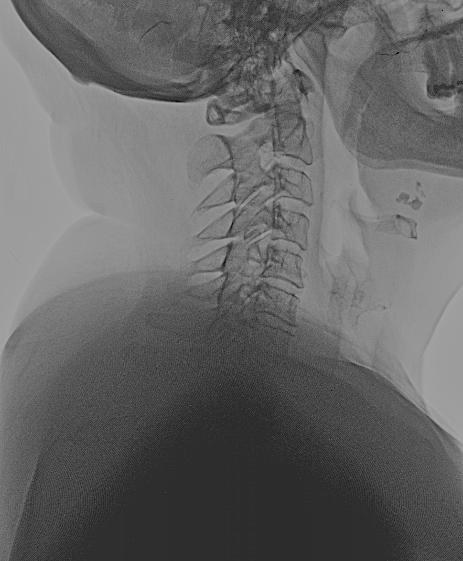

Control de 2 meses

Control 2 meses

Difícilmente se aprecia la prótesis

Copia con marcaje de los tornillos de la misma

En las RX lateral de control no se aprecia bien la caja atornillada, sin embargo, la paciente mejoró la clínica álgica y mostró recuperación funcional en MSD en los controles, por lo que decidí esperar a los 6 meses para la RM cervical.